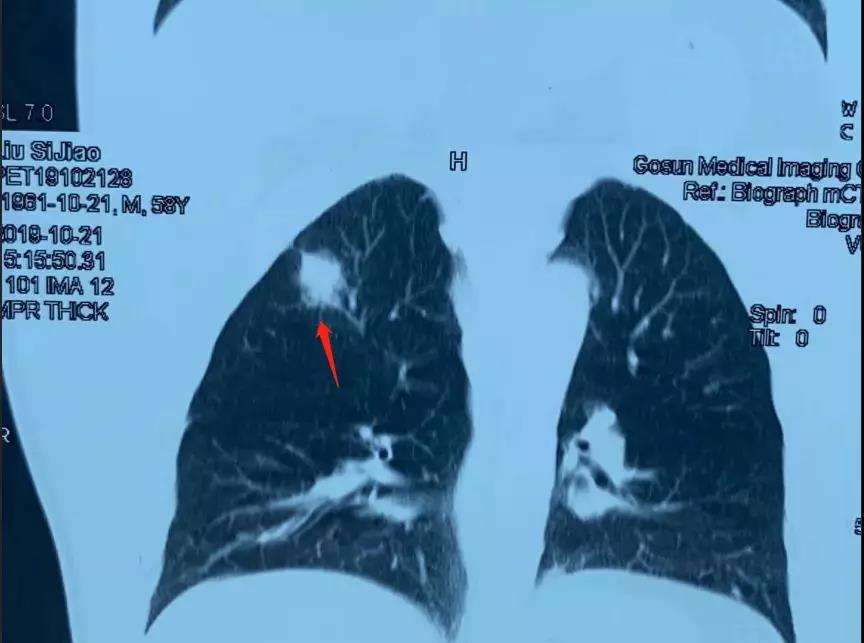

今年58岁的洪叔叔是一位原发性肺癌的患者,肿瘤的位置在右上肺,身体状况良好。可以承担手术,但是他本人比较恐惧做手术。在一位朋友的介绍下,洪叔叔来到了暨南大学附属复大肿瘤医院寻求冷冻消融的办法。

但是,通过CT检查发现洪叔叔不能排除有淋巴结转移的情况,经过复大的专家团队的评估,于这样早期的肺癌,冷冻消融的办法只能把原发病灶处理掉,但像洪叔叔对于这种有淋巴结转移的早期肺癌患者,手术还是首选,才可以达到根治的目的。为此复大的医生第一时间跟洪叔叔和他的家人谈了这件事情,可是洪叔叔还是表示很害怕手术,希望只做冷冻消融治疗,不接受手术的方案。

手术顺利行右上肺叶切除加系统性淋巴结清扫,术后病理分期是一个1A期肺癌,就是早期肺癌,病人完全康复出院,有望完全治愈。就这样,一个难关被攻克了。目前,洪叔叔身体状况良好。